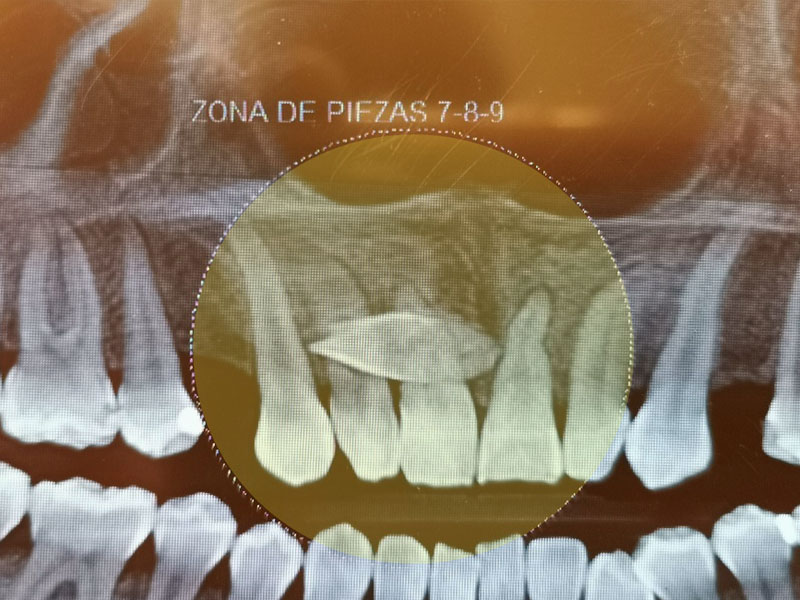

En el campo de la cirugía maxilofacial, la precisión diagnóstica es fundamental para planificar tratamientos efectivos y garantizar los mejores resultados. Durante décadas, las radiografías bidimensionales (2D) fueron la herramienta…